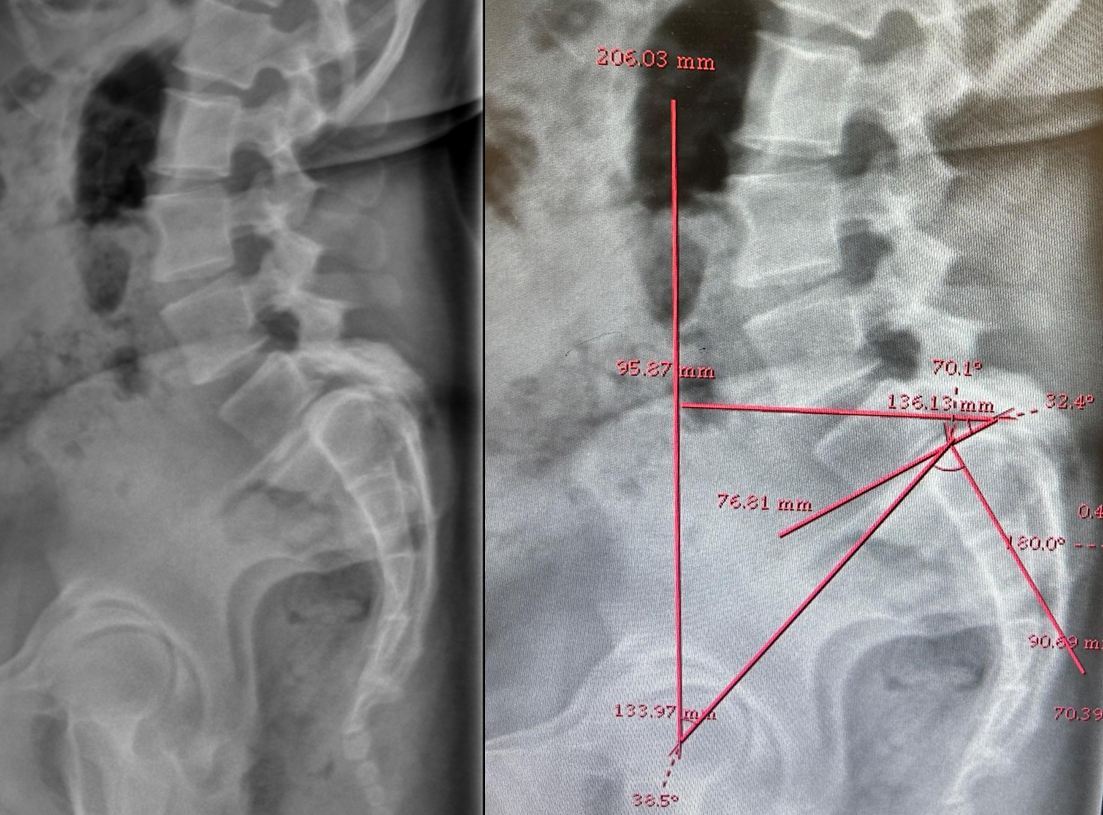

The patient had lumbar spine tenderness localized over the L4 and L5 vertebral levels. Lumbar spine range of motion (ROM) is painful on flexion and extension. Neurological examination showed positive Lasegue’s test at 40° on the right and 30° on left. Motor examination (5/5) in L1, L2, and L3 myotome bilaterally, with reduced power (4/5) in the L4, L5, and S1 myotome on both sides. Sensory examination showed normal sensation in the L1, L2, and L3 dermatomes, reduced sensation on the left at L4, and reduced sensation bilaterally at L5 and S1 S2 S3 S4 S5. Reflex examination showed diminished knee and ankle reflexes and plantar was mute on both side. MRI of lumbar spine with whole spine screening showed anterior listhesis of L5 over S1,central disc bulge,hypertrophy of the facet joints and ligamentum flavum caused severe central canal stenosis, lateral recess narrowing, compression of cauda equina roots, and severe bilateral foraminal stenosis with impingement of the exiting L4 nerve roots bilaterally (Figure1). Post-void residual urine volume is 232 cc on ultrasonography. Diagnosis was high dysplastic spondylolisthesis of L5 over S1, Meyerding Grade III, SDSG – Type 5 balance spine retroverted pelvics based on pelvic incidence 70o pelvic tilt 38osacral slope 32o (Figure 2). The high dysplastic according to the severity index.The patient was counseled on the need for immediate surgical decompression and lumbosacral stabilization to stop neurological deterioration. The recovery of bladder and bowel function was explained to be guarded due to the chronicity of symptoms. After getting informed and written consent the patient underwent posterior decompression and spondylolisthesis reduction with stabilization from L4 to S1, along with bilateral posterolateral fusion at L4-L5-S1 and posterior interbody fusion at L5-S1 under general anesthesia.We fixed L4 also, as the current case is an unstable zone.This zone was identified using a standing lateral radiograph of the lumbar spine that also captures the hips.On radiograph, square area is demarcated by drawing a horizontal line through the center of the S2 vertebral body. The boundaries of the line segment are determined by two vertical reference lines: one is the gravity line, which runs vertically through the midpoint of the inferior endplate of L5, and the other represents the ground reaction force, passing vertically through the center of the femoral head (Figure 3).

Figure 1